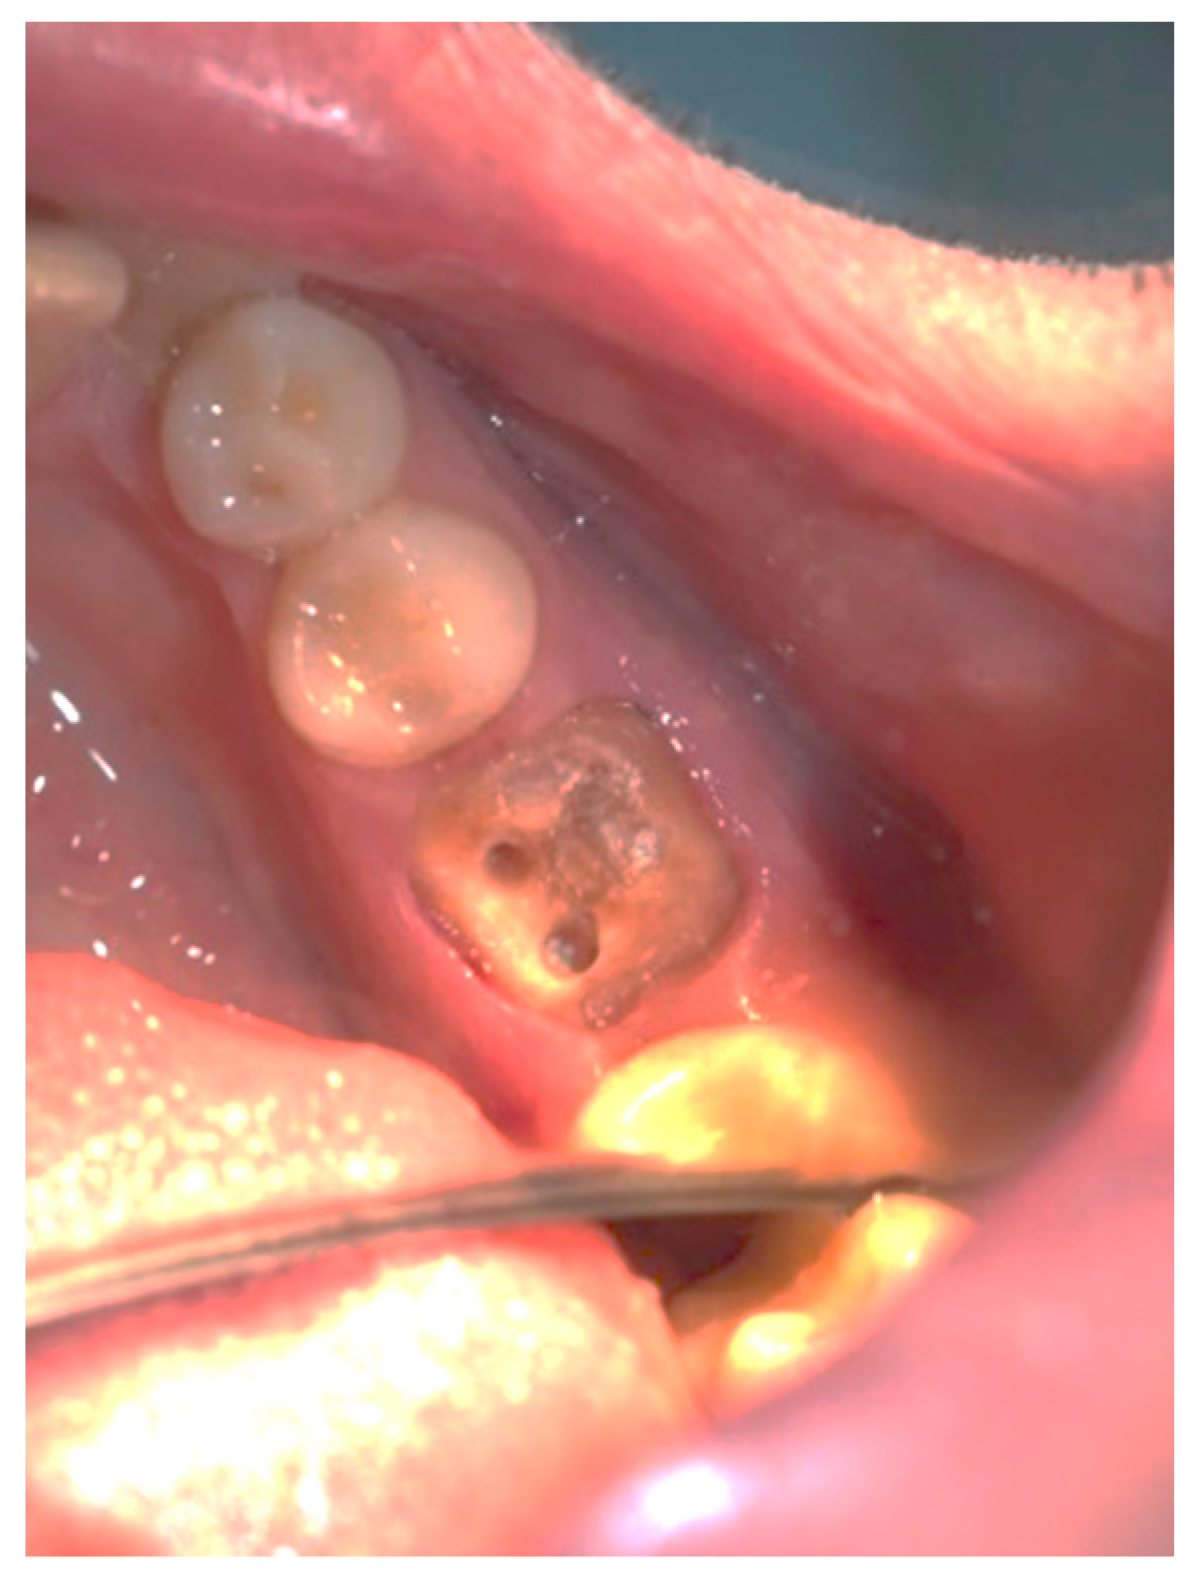

Figure 3, Figure 4, Figure 5, Figure 6, Figure 7 and Figure 8 display the follow-up of the healing process after a resective procedure for lengthening a short clinical crown with a laser.

Figure 5.

Healing at the 72nd hour: the wound was covered with fibrinous plaque and an erythematous halo.